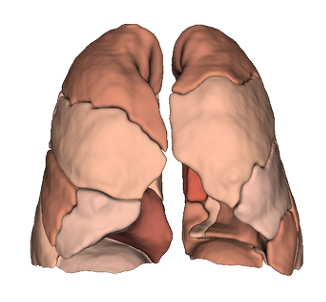

Lung Lobes

Anatomical segmentation

Pulmonary segments

Anatomical segmentation